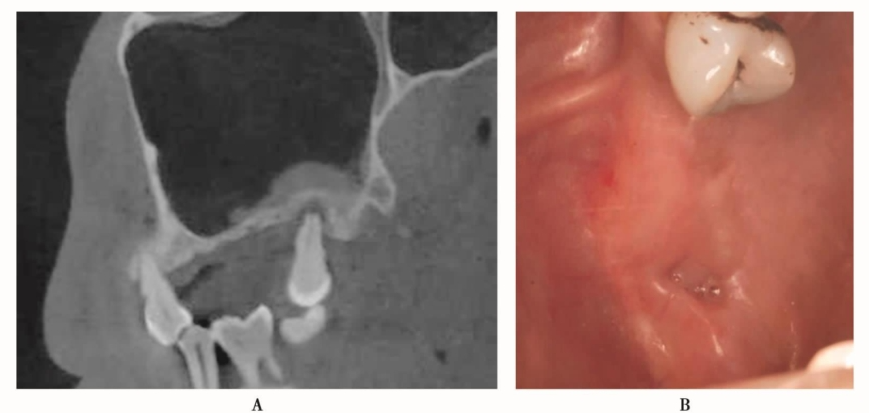

手术前CBCT检查显示患者窦腔内黏膜增厚,骨量严重不足,为保证骨增量效果,采用分期完成的方法,完成上颌窦窦底提升(图30、图31)。

图30 术前CBCT,上颌窦黏膜增厚明显A.冠状位;B.矢状位

图31 上颌窦外提升术后,CBCT显示植入的骨粉及增厚的黏膜情况A.矢状位;B.冠状位